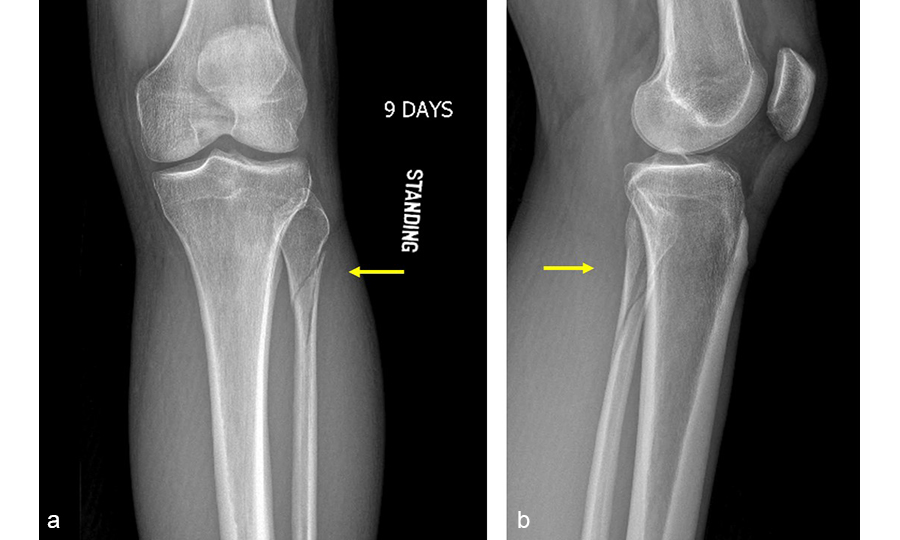

A 27-year-old man fell from a ladder sustaining a proximal fibula fracture (Fig 1) with a multipart posterior malleolar fracture (Fig 2). The patient was treated operatively with direct reduction and plate fixation of the posterior malleolar components. Intraoperative testing demonstrated continued syndesmotic instability requiring fixation (Fig 3). The syndesmosis was reduced in direct fashion and stabilized with a provisional K-wire and clamp before insertion of a FIBULINK Implant (Fig 4).